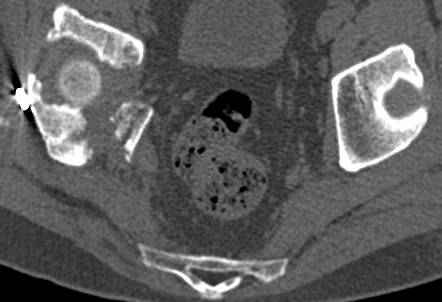

высылаю дополнительно сканы.

итак, второй вариант: высокий двухколонный с вовлечением КПС... Ни одно из основных повреждений не репонировано, кроме задней стенки. Скорее всего попытка реконструкции вертлуги сейчас будет очень травматичной и не очень эфективной, т.е. вероятный риск более значим, чем ожидаемая польза... Лучше подождать, и потом сразу эндопротез

>Вопрос к знатокам: Так что это?

к таковым себя не причисляю, но...обычное дело для нашей страны - выкладывать 3D и не показывать стандартные проекции Judet. Дигност представляет те ракурсы, которые по-его мнению наиболее информативны, более того комп сам достраивает какие-то мелкие повреждения по 3D по своему усмотрению. По данной реконструкции можно предполагать высокий двухколонный перелом с оскольчатыми передней и задней колоннами, оскольчатую высокую переднюю колонну с задним полупоперечником или одно из перечисленных с вовлечение КПС. У меня впечатление за второй вариант, но нужно обследовать нормально - проекции, сканы.